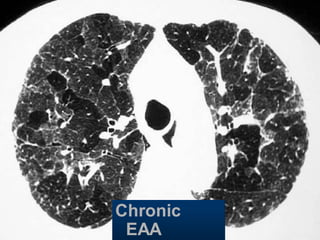

Chronic

EAA

Hypersensitivity pneumonitis Extr. Allerg.Alveolitis (EAA) HRCT Morphology chronic: fibrosis Intra- / interlobular septal thickening Irregular interfaces Traction bronchiectasis acute - subacute acinar (centrilobular) unsharp densities ground glass (patchy - diffuse)